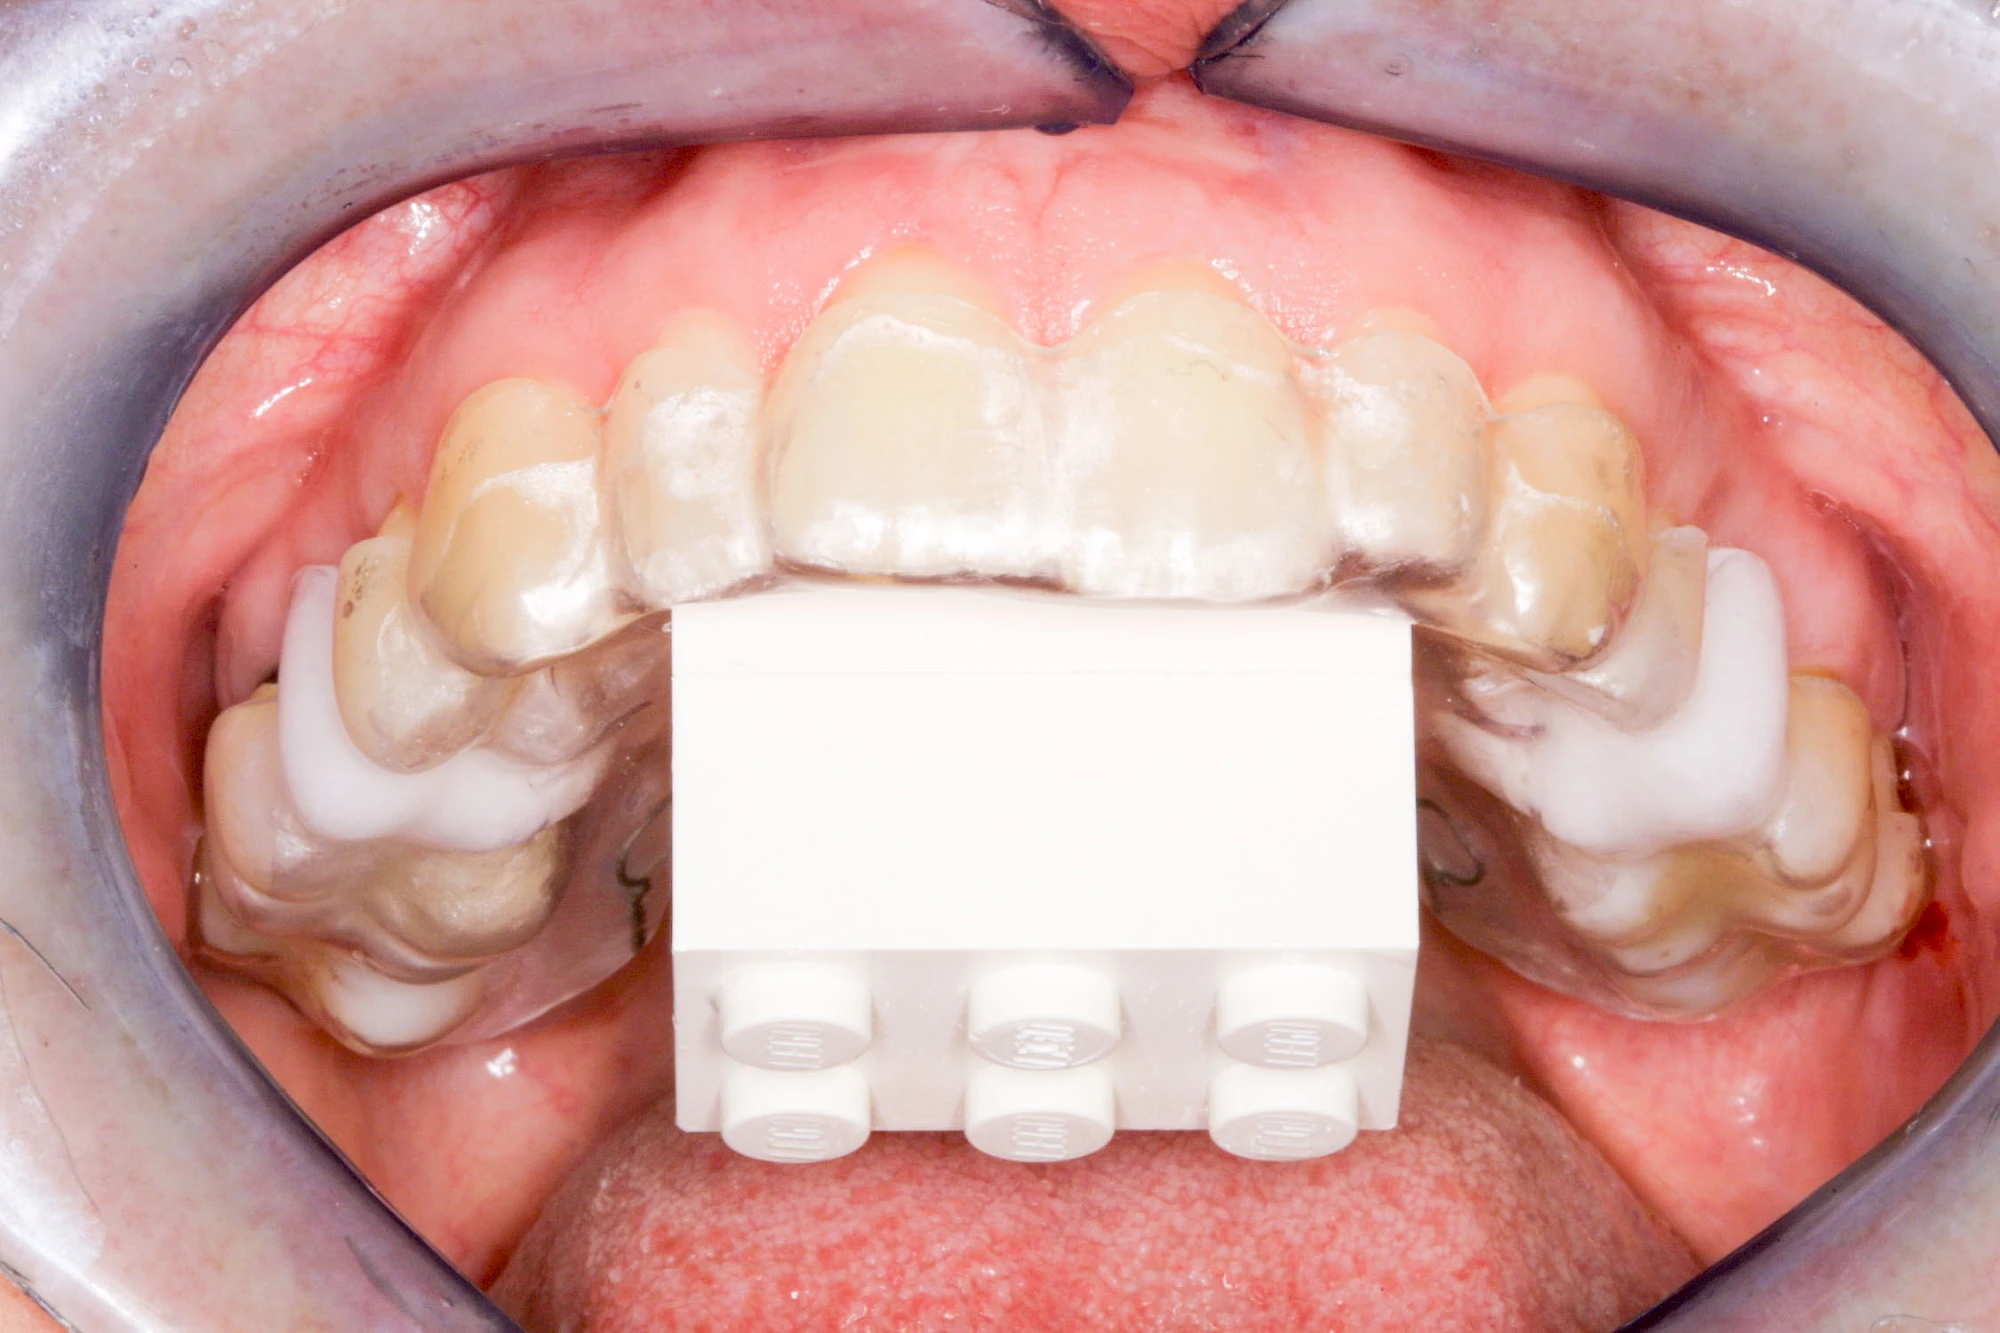

In diesen Fällen kann die Planung mittels verschieden aufwendiger Röntgen-Techniken (Übersichtsaufnahme, DVT) ggf. unter Zuhilfenahme speziell angefertigter Planungsschablonen sinnvoll sein.